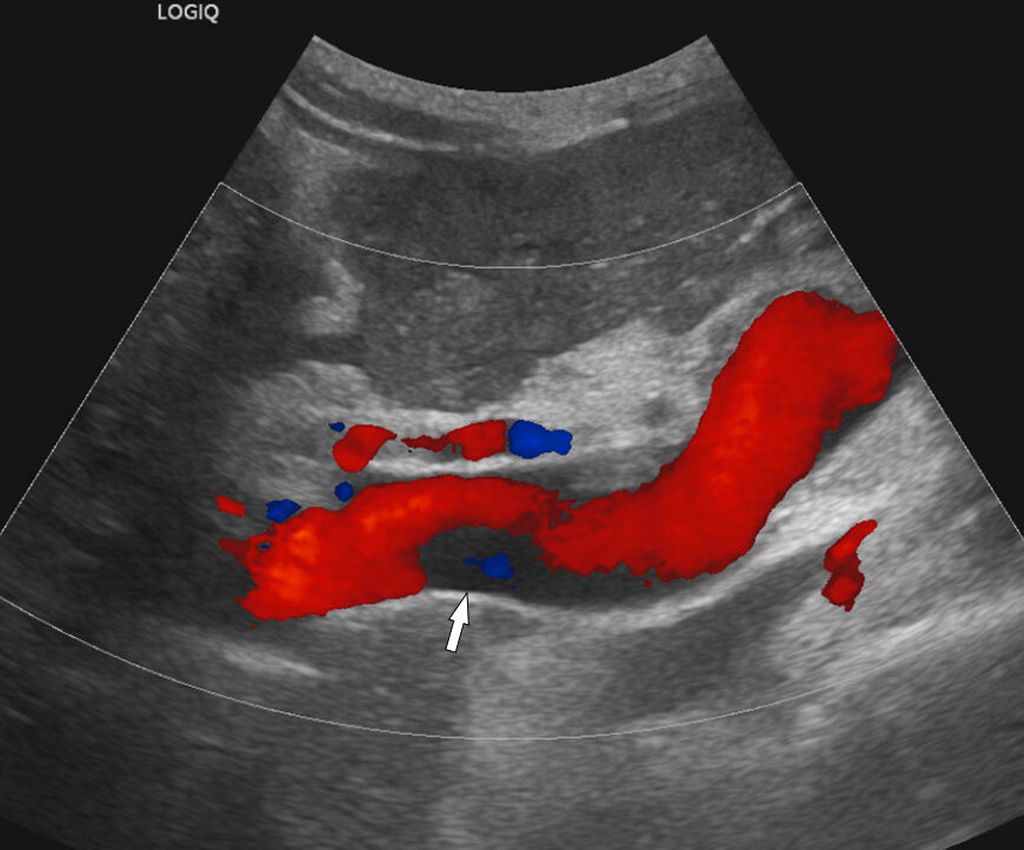

Abb. 1: Die farbcodierte Duplexsonografie zeigt einen wandständigen (nichtokklusiven) Thrombus (Pfeil) in der perfundierten Pfortader

Die bildgebende Diagnostik stützt sich auf die farbcodierte Duplexsonografie (Abb. 1), die Kontrastmittel-verstärkte MDCT (Abb. 2) und die MRT, wobei die MDCT die höchste Aussagekraft hinsichtlich Ausdehnung der PVT und Darstellung möglicher Komplikationen hat. Wichtig ist bei der MDCT die Anfertigung von 3D-Rekonstruktionen des MDCT-Datensatzes zur besseren Darstellung der Thromboseausdehnung (Abb. 2), im Vergleich zur ausschließlichen Darstellung auf axialen Bildern.